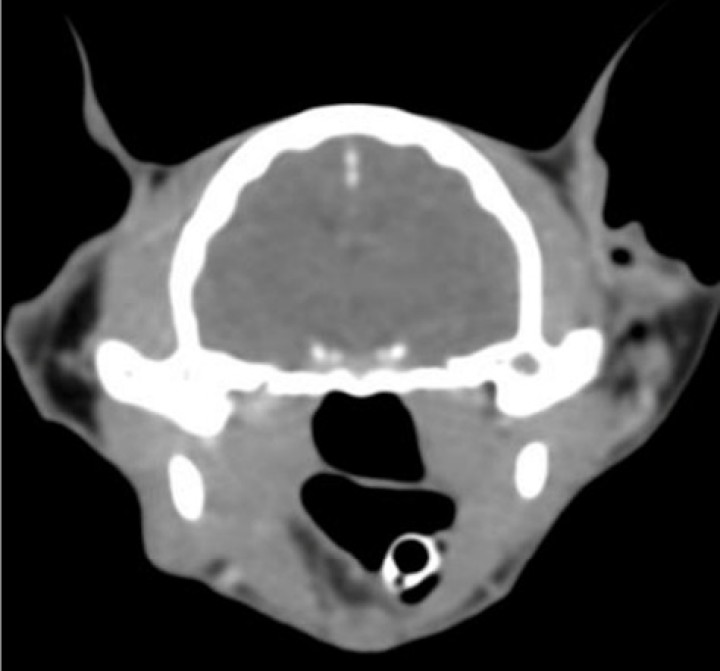

Imagen tomográfica transversa donde, a nivel intracraneal, no se evidencia ninguna lesión intra o extraaxial, no existe desplazamiento de la línea media, ni edema cerebral. La captación de contraste es normal y simétrica. Sin alteraciones meníngeas. Imagen cedida por el Hospital Bluecare.